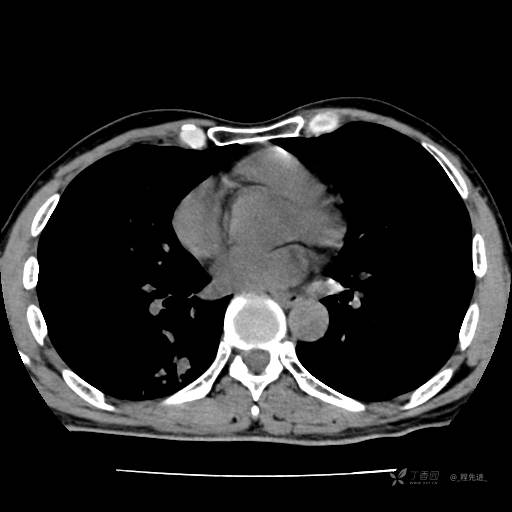

2月特别精彩病例|咳嗽、咳痰20余天,典型病例分享【结果已公布】

患者年龄:51岁

主诉:咳嗽、咳痰20余天

简要病史:20余天前开始出现咳嗽、咳痰症状,阵发性刺激性咳,白色粘痰,不易咳出,无发热,无咯血,无恶心、呕吐等不适,未诊治,咳嗽、咳痰症状持续存在。

体格检查:T:36.3 ℃ P:79 次/分 R:20 次/分 BP:128/64 mmHg,神志清楚,呼吸平稳,双肺呼吸音粗,右下肺闻及细湿性啰音。心率79次/分,节律整齐,各瓣膜听诊区未闻及病理性杂音。腹部未见异常,双下肢无水肿。

辅助检查:我院门诊胸部CT示:如下。心电图:窦性心律;正常心电图。